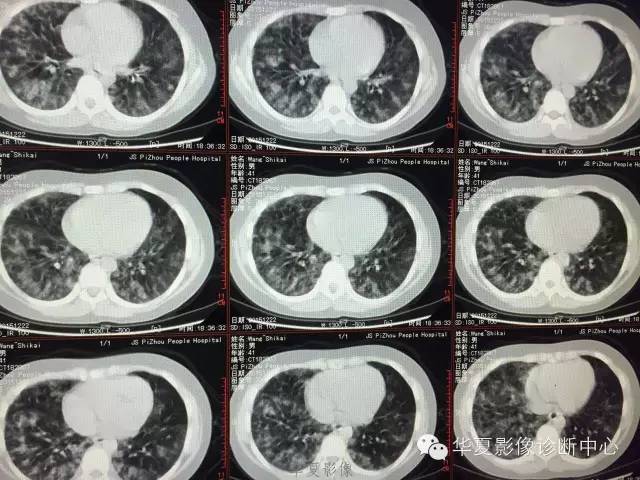

支原体肺炎1例CT影像表现

【病例】支原体肺炎1例CT影像表现